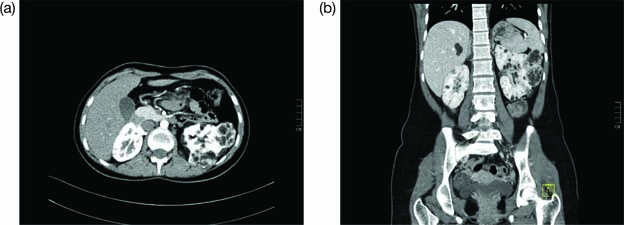

Polycystic kidney disease is characterized by the presence of an innumerable number of cysts that eventually occupy the renal parenchyma, culminating in renal failure and premature secondary hypertension. In most cases, diagnosis is established by utilizing clinical criteria; however, molecular genetic testing can be utilized for prenatal diagnosis, for screening family members of affected individuals, and for cases where diagnosis is ambiguous. According to the kidney-related surveillance and management recommendations by the International Tuberous Sclerosis Complex Consensus Group, MRI is the preferred modality for detection of renal cysts of ADPKD and TSC-associated AML, which is supplemented with frequent blood pressure screening and glomerular filtration rate (GFR) estimation (11). Renal US can be used to screen for AMLs and to monitor cysts; however, US can miss AMLs that are fat deprived or kidneys with numerous cysts. Thus, MRI of the kidneys may be preferable for clearer images (69). Figure 3 shows how a positive image of renal cysts looks like on an US. Children >12 years and adults have higher potential of developing AML and, therefore, should undergo an MRI every 1–3 years. In cases of TSC where initial MRI has exclusively ruled out the presence of AML, annual follow-up with US is recommended with an MRI every 2–3 years (70). In addition, genetic testing is recommended for TSC and ADPKD patients when they are presented with an ambiguous diagnosis (71, 72).

Figure 3: Ultrasound imaging reveals that both kidneys are enlarged with multiple cysts and loss of normal architecture, suggestive of polycystic kidney disease.